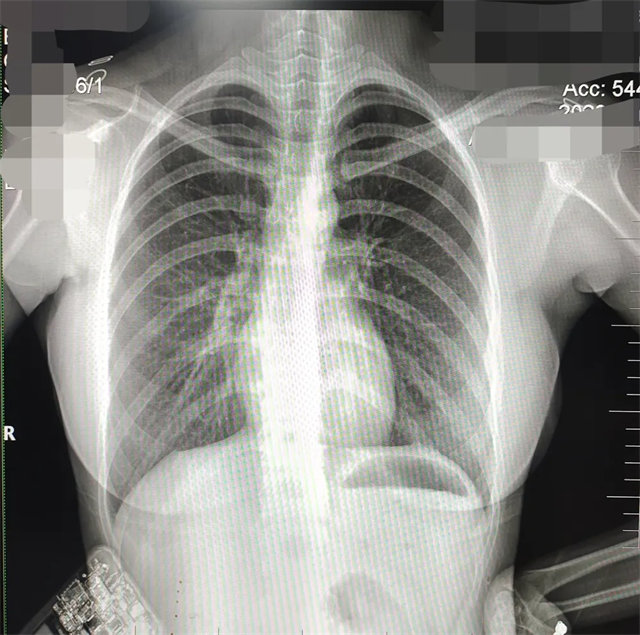

拍攝的不合格胸片的缺陷和解決方法

缺陷:兩肩胛骨未拉開肺野之外,吸氣不完全,且存在金屬飾品遮擋。

解決:去除金屬飾品及內(nèi)衣后重新按標準體位攝片即可。